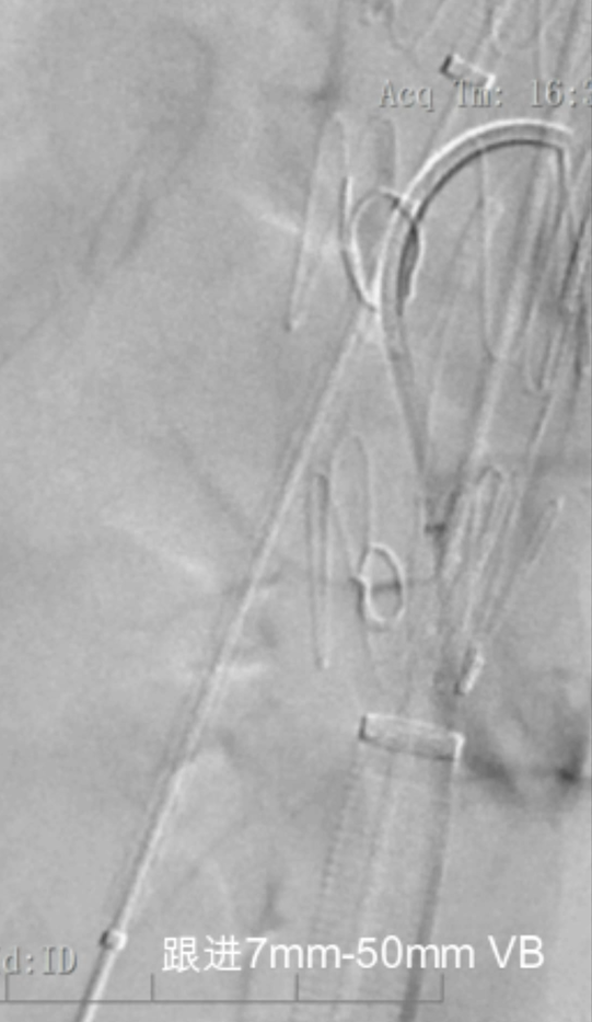

③ 桥接支架

自膨覆膜支架:具有更大的弹性,可随靶血管重塑而扩张

Viabahn:支撑性强,输送鞘短

SilverFlow:支撑性强,柔顺性好,输送鞘细

球扩覆膜支架:更大的支撑强度,能够以更小的位移而精确部署

VBX:支撑力不足,柔顺性高,适型性好

Lifestream:可以扩到的直径最大

BeGraft:径向力和灵活性较高

iCast:短缩情况最轻,覆膜破口风险最低,但支架较硬

裸支架:应用较少,非扩张区域

Express Vascular,支架扭结抗性相对较高

自膨覆膜+球扩裸支架

裸支架进一步提供支撑力,内衬,纠正扭曲